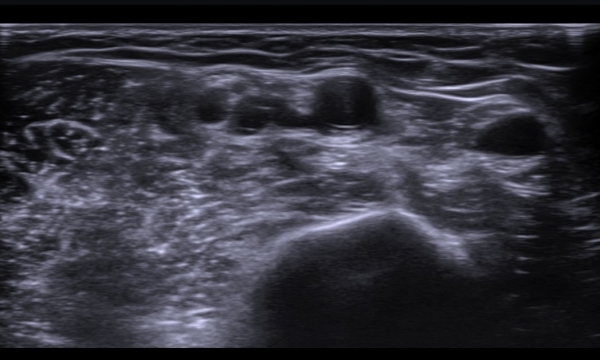

Á¤Á߽Űæ Ⱦ´Ü¸é°Ë»ç¿¡¼­µµ Á¤Á߽ŰæÀÌ Àú¿¡ÄÚ ºÎÁ¾ÀÌ ±æ°Ô  °üÂûµÇ°í ½ÇÁú³» ƯÁ¤ ¼¶À¯¼ÒÀÇ

Àú¿¡ÄÚ ºÎÁ¾ÀÌ ¶Ñ·ÇÇÏ´Ù(»çÁø 5, 6).